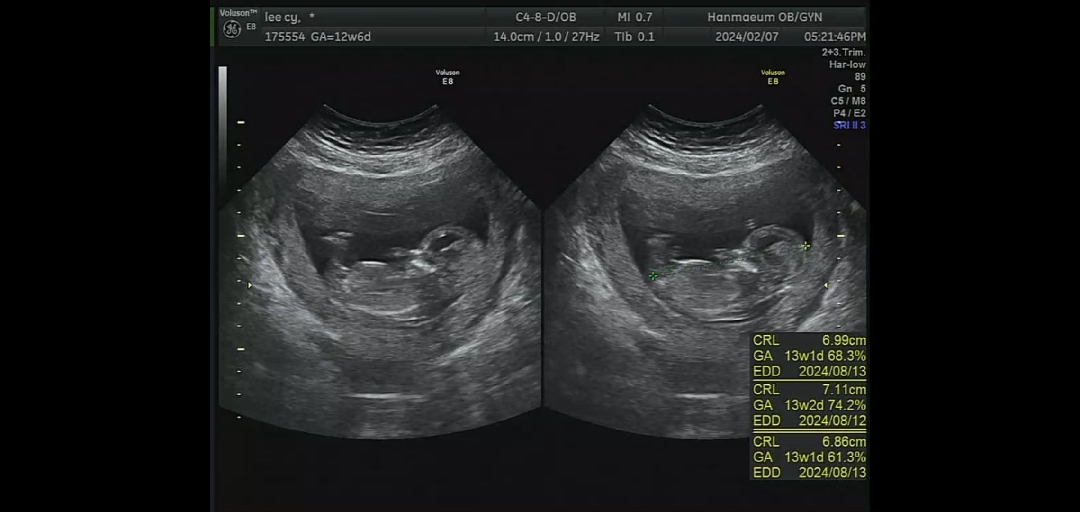

13부 성별 궁금한데...ㅜㅜ

이걸로 판별 가능 할가요..?!